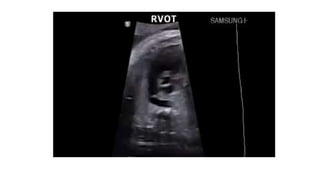

• #21 Cephalad sweep from the left ventricular outflow tract view would reveal the right ventricular outflow (blue arrow), which in a fetus with normal cardiac morphology crosses the left ventricular outflow tract (yellow arrow) at a right angle